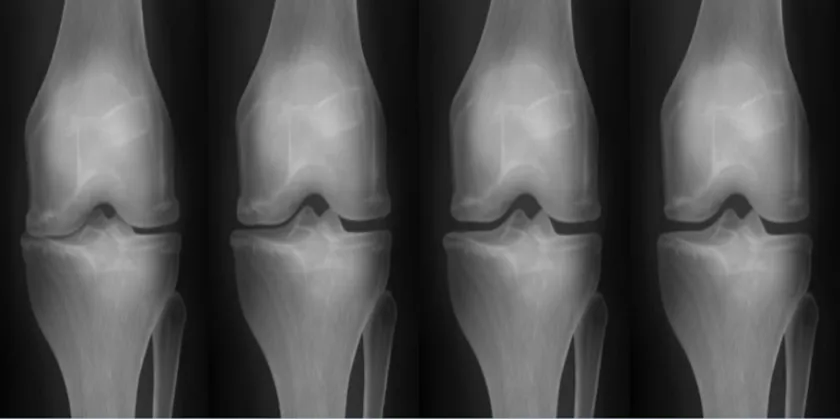

関節リウマチ(図1)や肝硬変(図2)など、特定の年齢層に限定されず、免疫力の低下で発生する可能性がある重症疾患の治療薬もやはりEHL BIOの核心研究分野です。両方の疾患ともに、既存の治療方式は「進行速度を遅らせること」に焦点を当てていましたが、EHL BIOが研究中の幹細胞治療剤の場合、患者本人の幹細胞の利用で免疫系拒絶反応を減らし「根本的な治療」が期待されます。

(図1)幹細胞施術前後の関節のレントゲン

脂肪幹細胞は何度培養しても遺伝子の変異がなく分化能力に優れているため、様々な自己免疫疾患の治療に利用されており、関節リウマチの炎症反応を抑制するのに効果的です。また、肝硬化幹細胞治療プログラムは、他人の幹細胞ではなく自分の脂肪幹細胞を使用するため、細胞拒絶反応や副作用がなく、安全に肝細胞を回復できる治療方法であり、一度の脂肪採取で十分な量の幹細胞を抽出して何度も治療できるという利点があります。